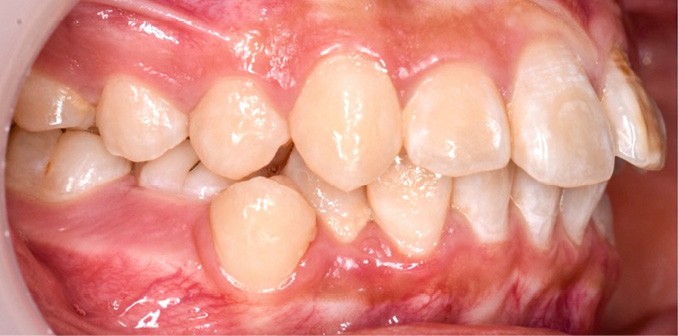

Une patiente âgée de 12 ans se présente en consultation, motivée par la position de son incisive centrale maxillaire, décrite comme « en avant », marquée par une dyschromie et une mobilité de grade 2 selon Muhlemann. L’examen clinique montre l’absence de 23 sur l’arcade, une dysharmonie dents-arcade marquée, un surplomb accentué, et une déviation des milieux inter-incisifs, conséquence du comblement spontané de l’espace de 23. L’ensemble s’inscrit dans un contexte de Classe I d’Angle molaire. L’orthopantomogramme révèle l’inclusion de 23, associée à une résorption radiculaire étendue aux deux tiers de 21. La 22 ne présente aucune altération visible.

La patiente, de profil normodivergent, présente une Classe I squelettique sans troubles fonctionnels (fig. 1-8).